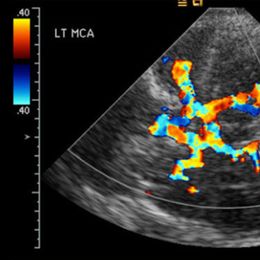

Mosier's team connected 17 healthy adults to functional magnetic resonance imaging (fMRI) -MRI scanning that shows real-time brain activity. The participants were then fitted with special computer-linked cybergloves that registered joint movements at 19 different points. Specific combinations of finger movements allowed them to move a cursor on a computer screen. By preventing the participants from relying on a mouse or touch pad to move the cursor, Mosier's team tried to simulate the challenges of brain "mapping"—the process by which the brain adapts to new, unfamiliar tasks.